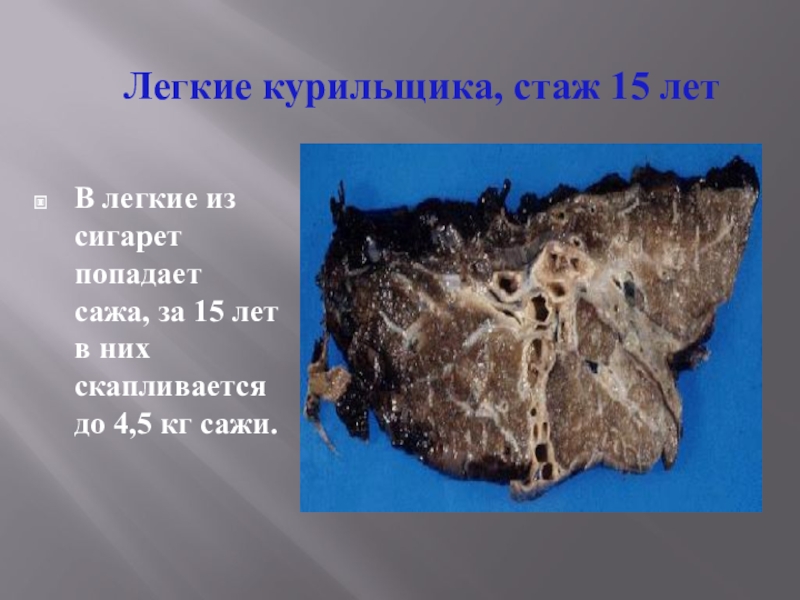

Здоровый образ жизни: Влияние курения

Раздел: Моменты озарения